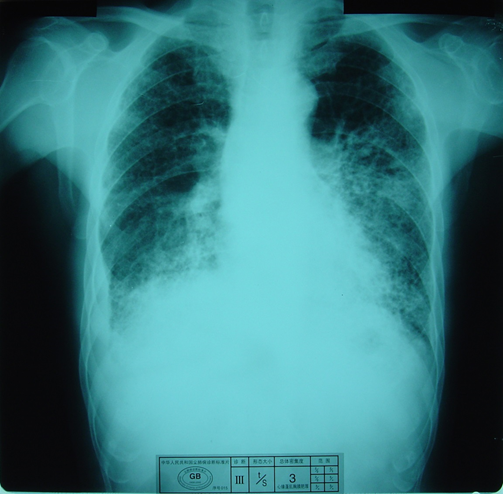

(3)X射线胸片表现 主要表现为不规则小阴影和胸膜改变。不规则小阴影是石棉肺诊断分期的主要依据。早期多在两肺下区出现密集度较低的不规则小阴影,随病情进展,小阴影逐渐增粗、增多,呈网状并逐渐扩展到两中、上肺区。

不规则小阴影

晚期石棉肺可因纵隔胸膜增厚并与心包膜及肺组织纤维化交错重叠,致使心缘轮廓不清,甚至形成“蓬发状心影”,此影像是“叁”期石棉肺的主要诊断依据之一。

石棉肺叁期( “蓬发状心影”)